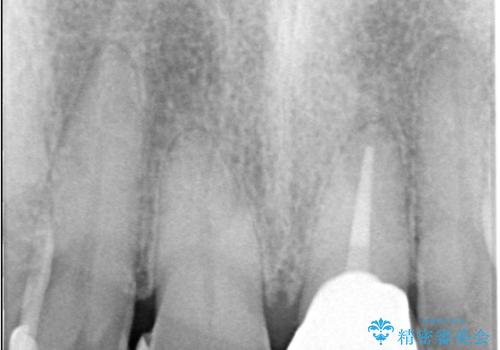

- 歯髄が死んで変色していた歯に対して、根管治療とオールセラミッククラウンでの修復を行いました。まず、根管治療で内部の感染を除去し、歯の強度を高めるためにファイバーコアを装着しました。その後、審美性と耐久性を考慮し、オールセラミッククラウンで覆うことで、自然な歯の色合いに近い美しい仕上がりを実現しました。

歯髄が死んだ歯は通常の健康な歯に比べて透過性が低く、特有の暗い色調を帯びる傾向にあります。変色は時間とともに進行し、薄い茶色や灰色、黄色がかった色合いになることが多いです。このような変色は、審美的な面で気になる場合が多く、オールセラミッククラウンなどでの修復が行われることも一般的です。